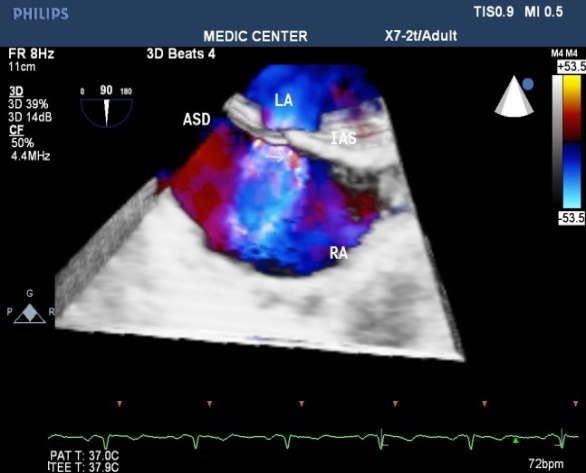

Multiple ASDs account only 4%, 3D TEE with wide sector can detect and visualize all the shunts through IAS (Figures 22-37).

Figure 29. Multibeats live mode with color fow mapping visualizes the L-R shunt

Figure 30. SVC sinus venosus ASD with L-R shunting

Figure 31. IVC sinus venosus ASD with L-R shunting

Figure 32. Secundum ASD viewed from LA